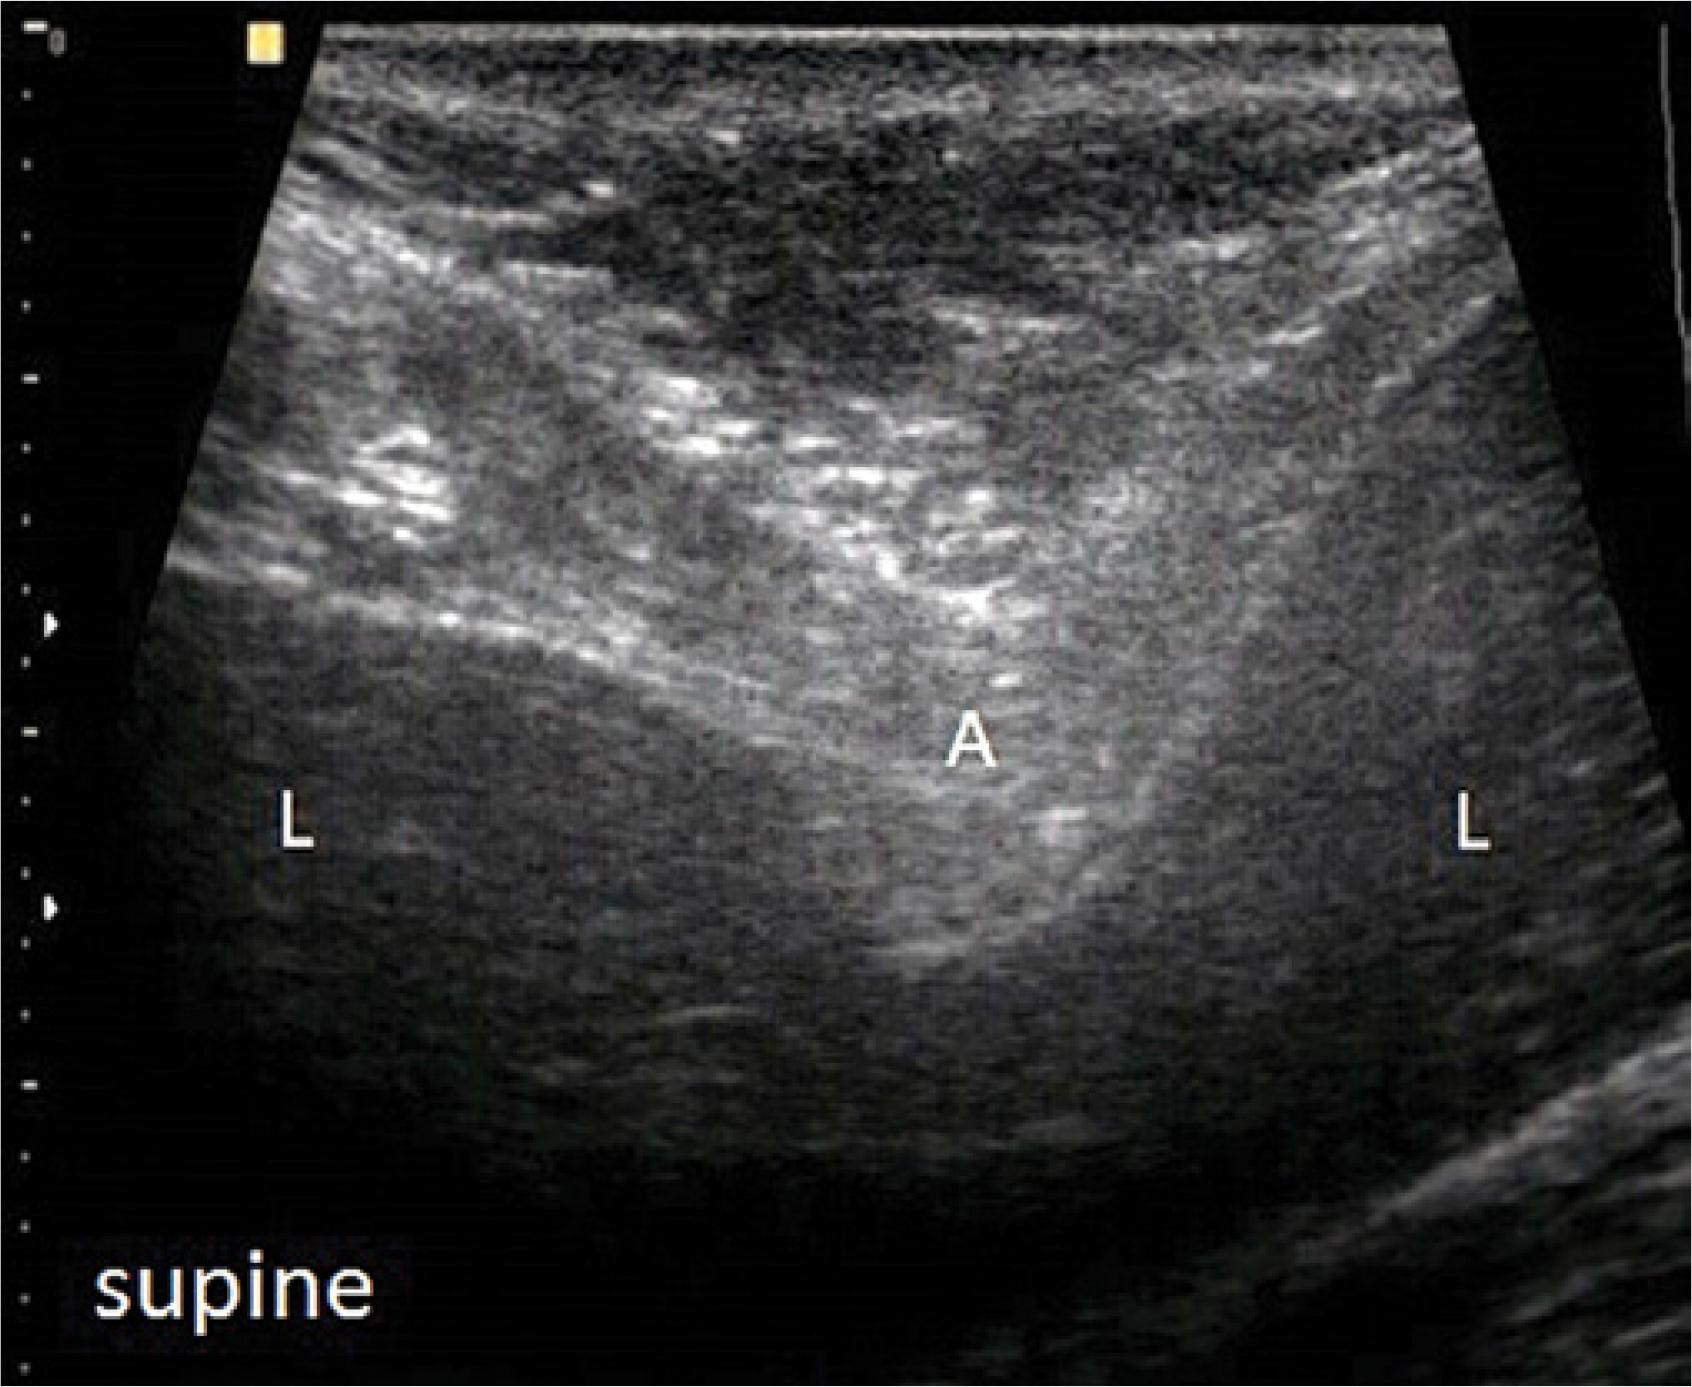

Fig. 2